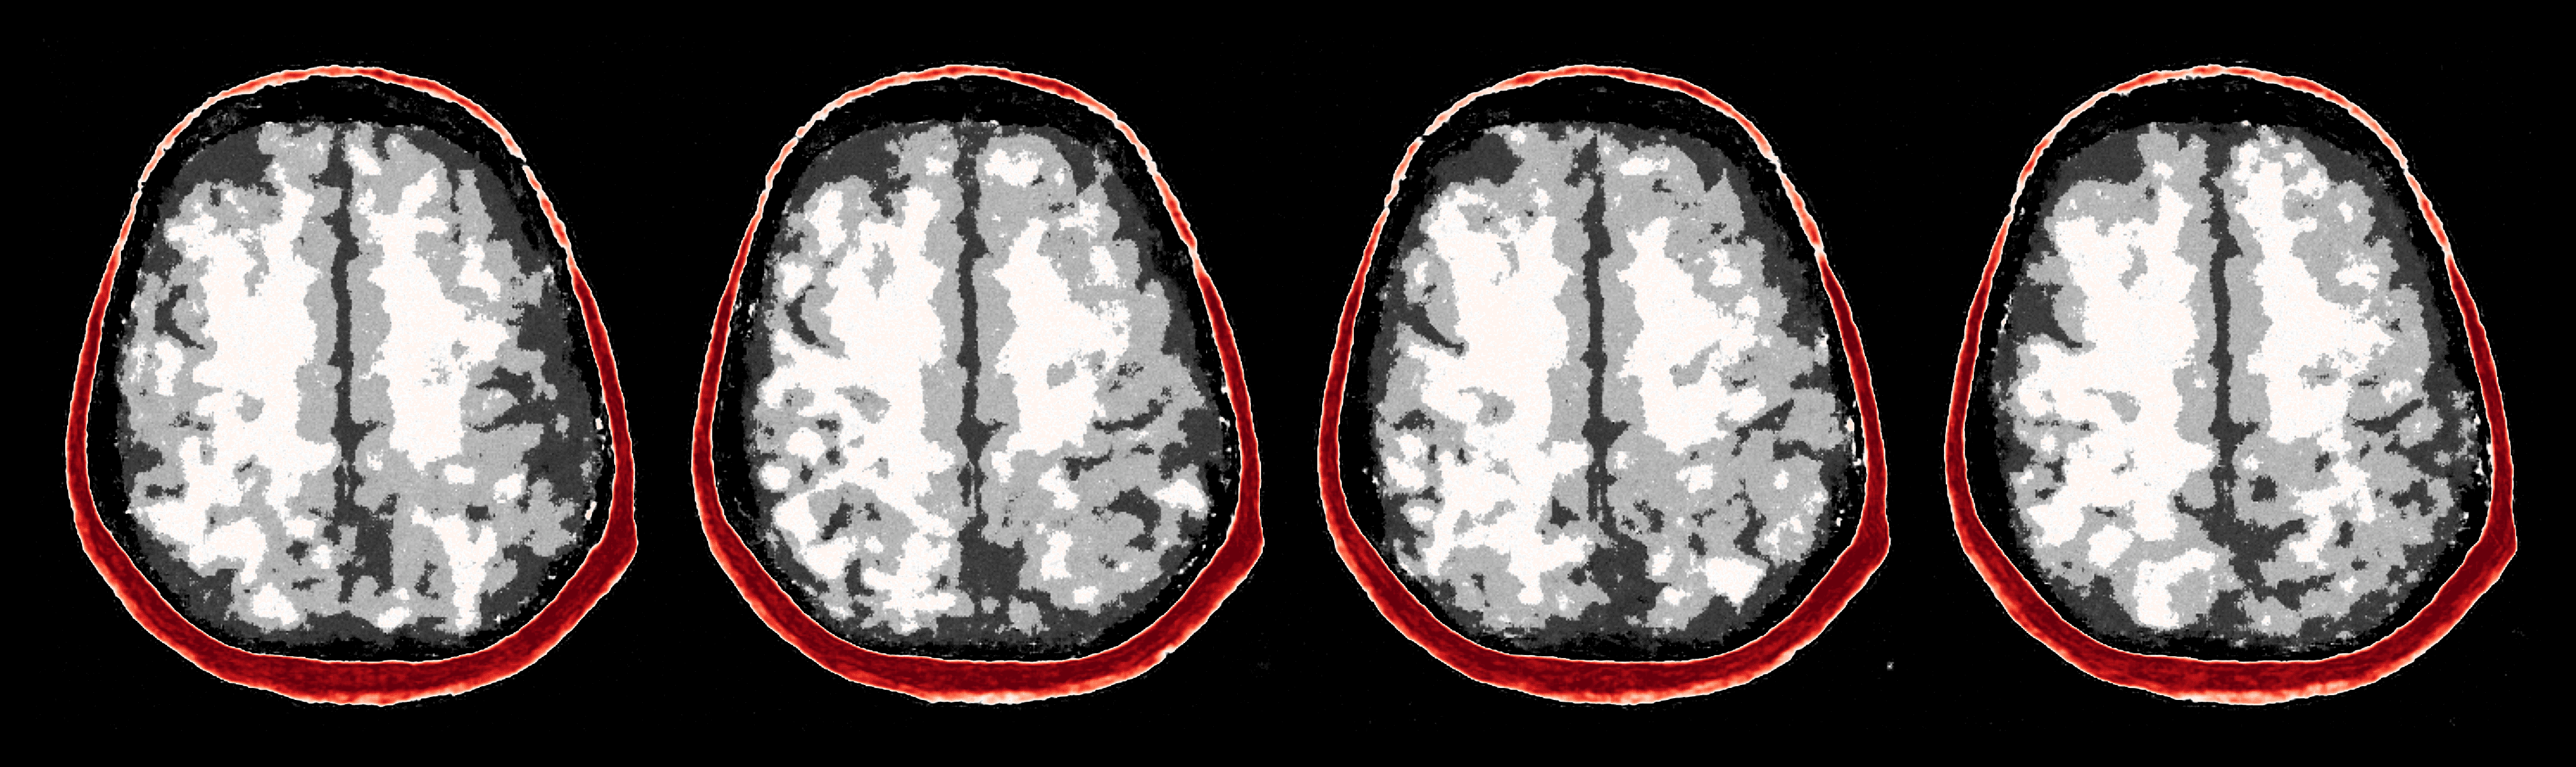

To overcome the end-to-end inference problem, we apply one iteration of ASPIRE by training a CNF on pairs, , where the ’s represent the score-based summary statistics at the fiducial points, , taken to be the uniform water velocity for all samples. An example of this initial summary statistic is shown in Figure 8. While the outer edge of the skull is reasonably well delineated, the inner edge of the skull is still poorly resolved and details inside the skull are mostly absent. However, the inference based on these initial summary statistics, shown in Figure 9, present a significant improvement over the baseline (cf. Figure 7), despite the presence of strong imaging artifacts in the summary statistics. The improvements concern the skull’s structure in particular, although details within the skull remain elusive due to the summary statistic’s limited information. To enhance fidelity further, ASPIRE 2 (shorthand for ASPIRE at iteration ) is applied by recalculating the score at the new posterior mean estimate for each training sample. Given these new training pairs, the next CNF is trained. While posterior sampling is efficient with CNFs (using Equation 4), recalculation of the score for each sample is computationally intensive, a topic we address in Section 6.6.

After the refinements of ASPIRE 2, significant improvements are evident in the posterior samples, particularly in capturing the structures within the brain tissue itself. The mean of these posterior samples, displayed in Figure 10, is clearly enhanced in resolution and details. We attribute these enhancements to the increased informativeness of the summary statistic in the second iteration compared to the information yielded by the initial iteration. A detailed inspection of the second summary statistic (shown in Figure 8) reveals more detail on the internal brain structures. Unlike the first summary statistic (cf. Figure 8), which primarily delineated the skull, the second iteration’s summary statistic better ‘illuminates’ the softer tissues within the brain, offering a more informative image for the posterior network. Thanks to accounting for the scattering at the skull, the acoustic illumination of the brain is improved significantly. Accurately resolving the skull structure is an important consideration as noted by [65].

As one can observe from Figure 10, the reconstruction quality improves for increasing number of refinements of ASPIRE. By virtue of the iterative recalculation of the score-based summary statistic, the method is progressively able to discern finer details within the brain albeit the updates become less pronounced as the number of refinements increases. We further illustrate this refinement by plotting posterior samples from all four ASPIRE iterations in Figure 21. Practically, a user of ASPIRE can decide on the number of refinements based on the amount of compute available or by refining until there are diminished returns on enhancements.